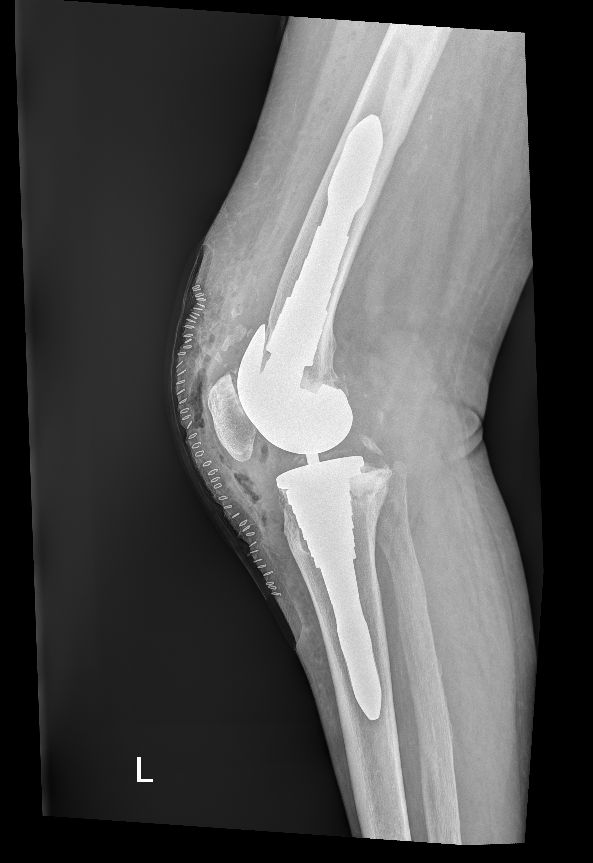

Da quando ha preso servizio presso l’Ospedale del Delta si è sempre occupato della chirurgia protesica del ginocchio sia monocompartimentale che totale acquisendo esperienza anche sulle tecniche basate sulla navigazione assistita che sull’impianto di protesi custom-made. Di routine esegue interventi di chirurgia artroscopica per il trattamento delle patologie meniscali e cartilaginee e di ricostruzione del legamento crociato anteriore mediante varie tecniche